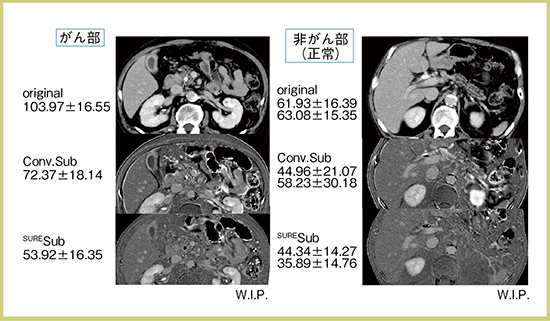

SURESubtraction Iodine Mappingは膵臓にも応用できる。膵頭鉤部がんで閉塞性膵炎改善後の症例(75歳,男性)に,従来法とSURESubtraction Iodine Mappingのサブトラクションを適用した(図3)。これはECV mapではなく単純なサブトラクションであり,病変間,もしくは疾患間ではあまり差がないように見える。

図3 膵頭鉤部がん+閉塞性膵炎改善後の症例に対する従来法と

SURESubtraction Iodine Mappingの比較